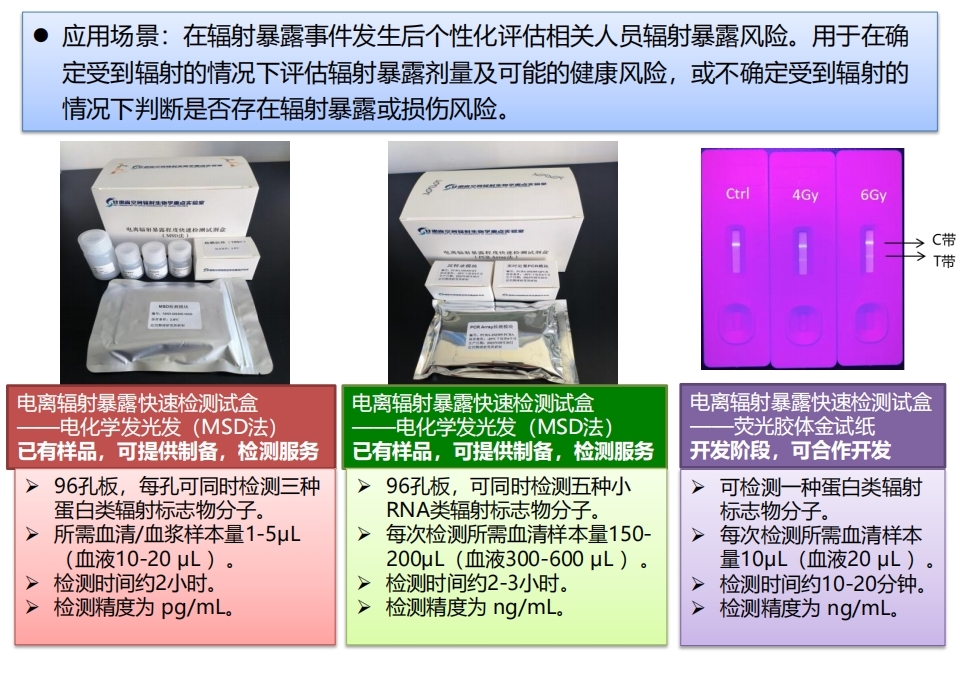

受到电离辐射后,机体的器官和细胞会分泌大量的生物分子(蛋白或RNA等)进入循环血,通过检测这些分子的血液水平并结合相应的模型预测可以有效评估个体的辐射暴露剂量及可能面临的健康风险等信息。本成果包含多种通过组学筛选和验证得到的血液辐射标志物分子,对光子(X射线或γ射线)、质子和重离子辐射都十分敏感,在0.1Gy—8Gy的剂量窗口(等效X射线剂量)和辐射暴露后6小时—7天的时间窗口内,能有效反映个体的辐射暴露风险。针对这些分子,已研发三款微创的快速检测试剂盒,所需血液样本量为50微升,检测时间为15分钟-3小时。